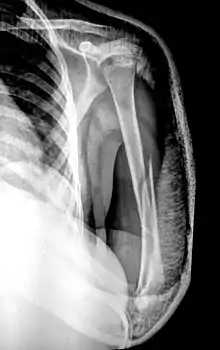

Рентгенограмма при диафизарном переломе плеча. Переломы плеча в среднем отделе (диафизарные переломы плеча) возникают в результате падения на руку или удара по плечу, могут быть косыми, поперечными, винтообразными и оскольчатыми. Диафизарные переломы плеча нередко сочетаются с повреждением лучевого нерва. Возможно повреждение плечевых артерий и вен.

- Симптомы

Клиническими признаками перелома плеча являются боли, отёчность, деформация, крепитация костных фрагментов и патологическая подвижность плечевой кости. При переломах плеча с повреждением лучевого нерва пациент не может самостоятельно разогнуть пальцы и кисть. Для уточнения диагноза и выбора тактики лечения выполняют рентгенографическое исследование.

- Лечение

Переломы плеча без смещения фиксируют гипсовой лангетой, с последующей её заменой на закрытую повязку типа «Дезо» или «Вильпо». При этом контролируется сопоставление отломков с помощью рентгенограмм в разных проекциях. Общий срок иммобилизации при консервативном лечении диафизарных переломов плечевой кости составляет 3-3,5 месяца.

Консервативное лечение целесообразно только в редких случаях: при переломах без смещения или при минимальном смещении отломков, а также при возникновении противопоказаний к операции. В остальных случаях показано оперативное лечение, так как современные малоинвазивные и другие методы фиксации позволяют уже через 3-4 недели начинать разработку движений в плечевом и локтевом суставах, что в свою очередь, предупреждает возникновение тяжёлых контрактур в этих суставах. При повреждении лучевого нерва вследствие перелома проводят оперативное лечение с обязательной ревизией нерва, с адекватной фиксацией отломков.

Хирургическое лечение также показано при многооскольчатых переломах плеча, невозможности закрытой репозиции, интерпозиции мягких тканей и повреждении сосудов и нервов. Фиксацию отломков осуществляют при помощи пластин, интрамедуллярных штифтов с блокированием, или аппарата Илизарова.